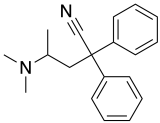

Open chain opioids

Amidones

- Dextromethadone

- Dipipanone

- Isomethadone=

- Levoisomethadone

- Levomethadone

- Methadone

- Methadone intermediate

- Normethadone

- Norpipanone

- Phenadoxone (heptazone)

Structures